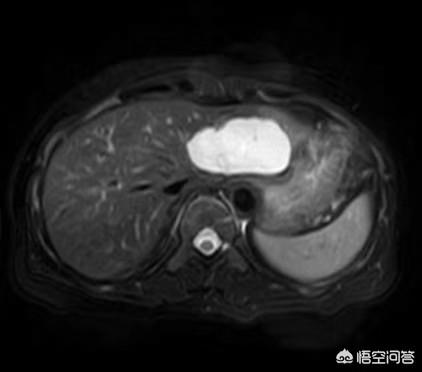

Die meisten kavernösen Hämangiome werden zufällig bei der körperlichen Untersuchung per Ultraschall entdeckt. Typische Läsionen haben charakteristischere Bilder auf Ultraschall, CT und MR, und eine qualitative Diagnose ist nicht schwierig. Bei der Ultraschall- und CT-Anreicherung sind sie typischerweise "early out and late in", und beim MR-Scan T2 ist ein "Glühbirnenzeichen" zu erkennen (siehe unten).